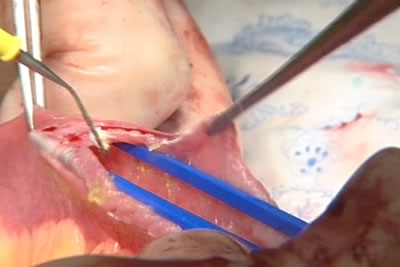

Начат этап формирования нового мочевого пузыря из тонкого

кишечника. На снимке показан Меккелев дивертикул.

Линейкой оператор отмеряет нужный участок тонкого кишечника

для мочевого резервуара.